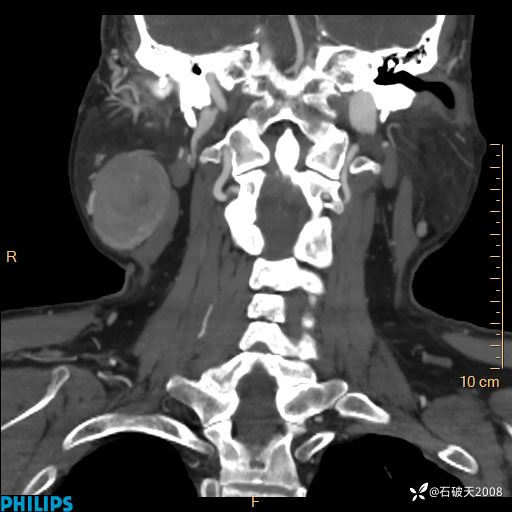

静脉期